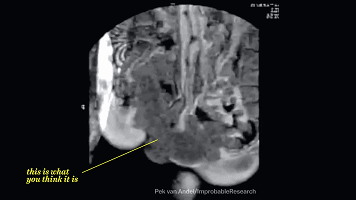

下面这个图就是啪啪啪的关键过程了。

这时候,我们的血液流动会重新分配,血液会在短时间内聚集在体表,导致皮下毛细血管血流更加丰富。

这使你的皮肤表面敏感度和感受比平时更加明显,肌肉开始从不规律性收缩转向为有规律的收缩。

(这张动图,嗯,就是你想的那个意思)